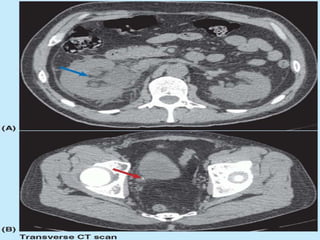

The urinary bladder develops during the 18th week of fetal development. It is located in the pelvic cavity behind the pubic symphysis in males and anterior to the uterus in females. The bladder has a muscular wall and receives its blood supply from branches of the internal iliac artery, including the superior and inferior vesical arteries. Nerve supply comes from pelvic splanchnic nerves via the hypogastric plexus and pudendal nerves. The bladder drains lymph into pelvic lymph nodes and is supported by ligaments attached to surrounding structures in the pelvis. Microscopically, it has a mucosa, submucosa, muscularis and adventitia layers.